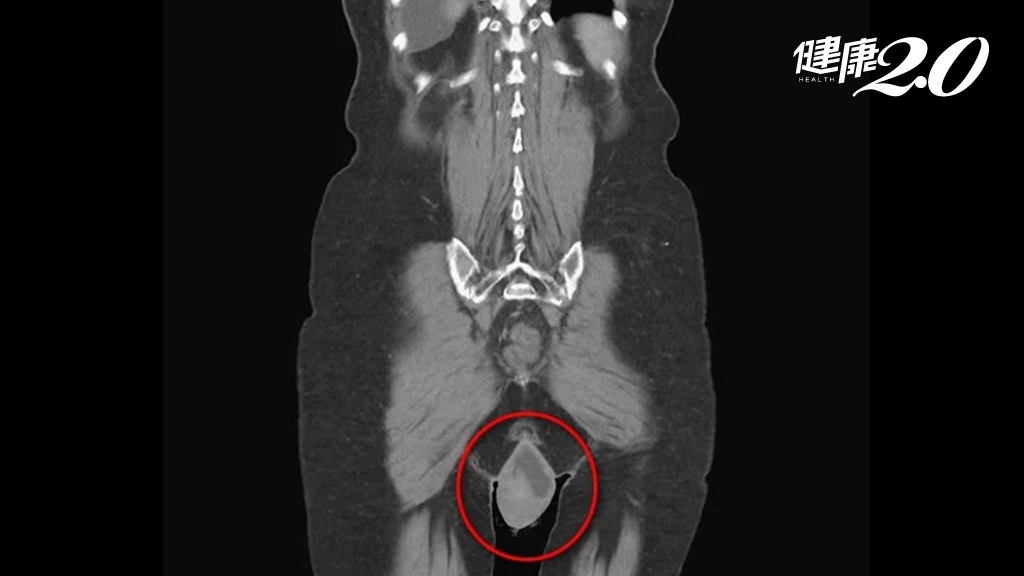

心電圖、胸部X光、心臟超音波均可檢查心臟衰竭

一般我們可以利用心電圖、胸部X光檢查,確知病患心律與心臟大小,若胸部X光檢查發現有心臟擴大或肋膜積水現象,大多已有心臟衰竭。另外,心臟超音波也是常用的檢查項目,用以量化、確認心臟收縮與舒張功能,並藉此檢查瞭解可能的心臟衰竭原因。若要進一步瞭解是否是有冠狀動脈血管疾病,就須再安排心導管檢查。